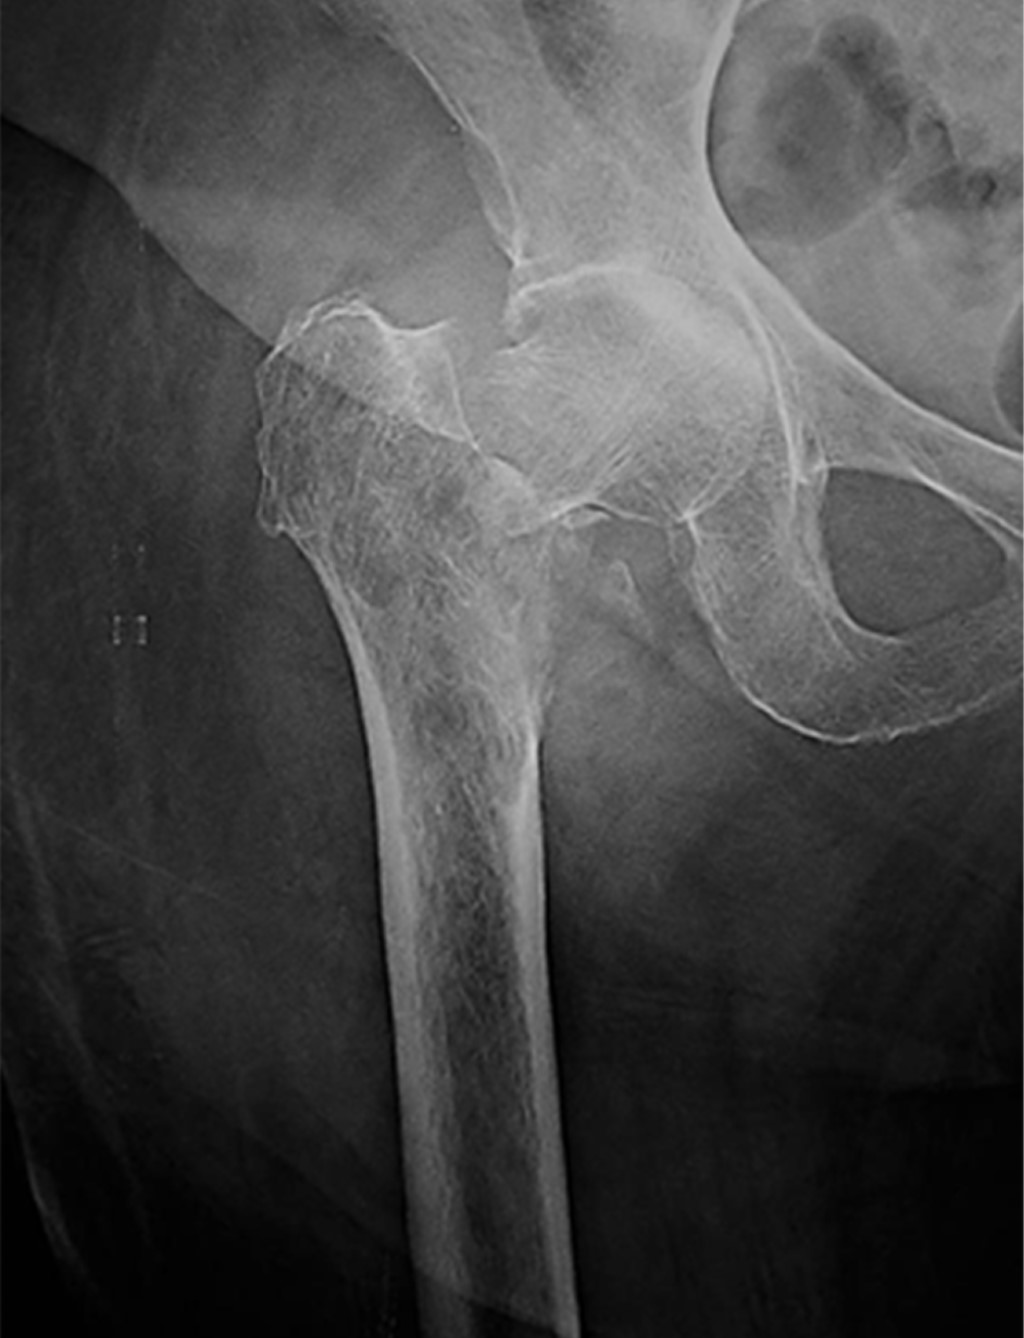

Bone metastases from a primary cancer of any part of the body are the most common form of malignant bone tumor constituting approximately 70% of them. The proximal femur being the most common extra-vertebral location for its location; 10% of patients have some pathological fracture, which is a serious complication. Currently the objectives of the treatment of a pathological fracture are: resection with adequate oncological margins, that the patient survives the surgical intervention, maintain the functionality, that the placed implant has a longer life time than the patient. The use of non-conventional hip prostheses is an excellent treatment option fulfilling the 4 established objectives, therefore this case is presented in which a right bipolar hip hemiarthroplasty is performed with a non-conventional prosthesis where it was treated with a described complication and the surgery of resolution.

Figure 4